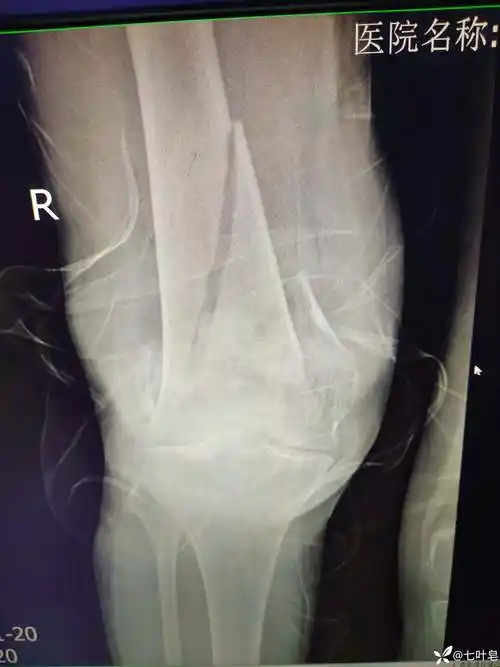

股骨髁上髁间粉碎性骨折

股骨髁间粉碎性骨折(c2型)

股骨髁间骨折

股骨髁粉碎骨折

左股骨髁间髁上粉碎性骨折 [病例帖]